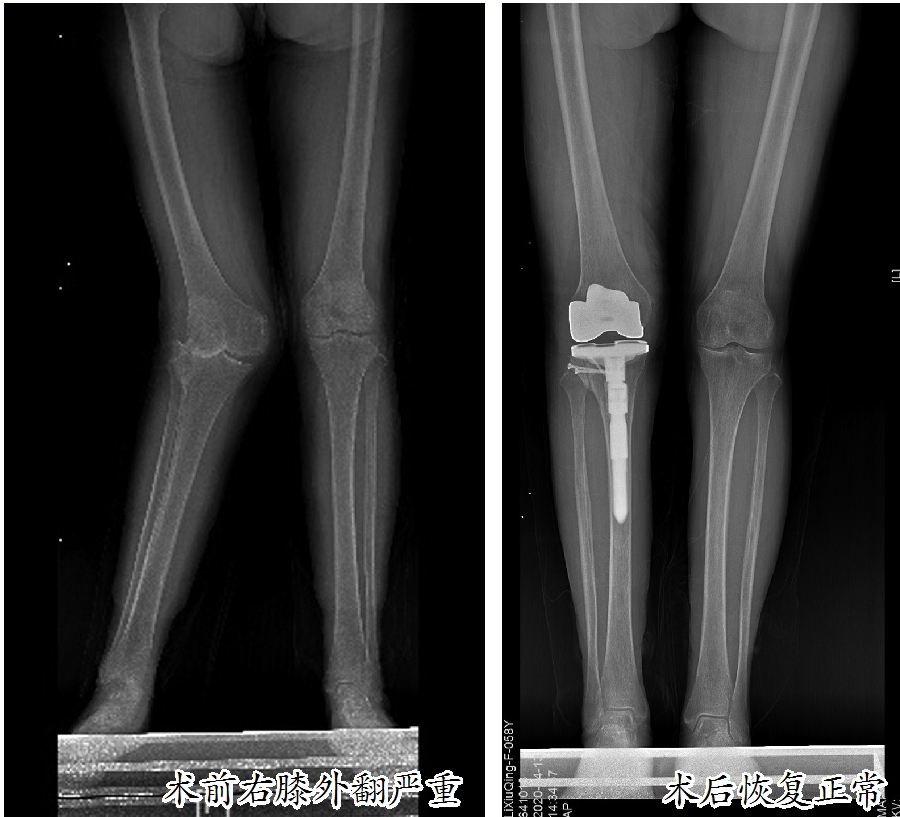

手术之前,患者右侧下肢关节肿大,严重外翻畸形,靠着墙边站立时呈“K”型腿,走路时“一摇三晃”,呈现出明显的“鸭步”,走到哪里都是“焦点”;

手术后经过锻炼和恢复,患者已经与常人无异,“脚下生风”恢复活力,自信和乐观重新回到了她身上。

这名患者名叫李素严(化名),患有类风湿性关节炎多年,近半年感觉双侧膝关节疼痛严重,影响了日常生活,来到市人民医院骨科中心关节外科、运动医学科就诊。入院后,经过双侧膝关节X线检查发现:双膝关节存在不同程度的退行性变,其中右膝关节退化严重,重度外翻畸形,外翻角度超过30度,属于重度膝外翻,已经到了必须治疗的地步。

膝外翻又称为“X型腿”“K型腿”或“碰膝症”。在医学上,正常人的膝关节有5至7度的外翻角,如果超过此角度就是病态。膝关节向外侧倾斜10至15度为轻度外翻,超过15至30度为中度外翻,外翻角大于30度为重度外翻。